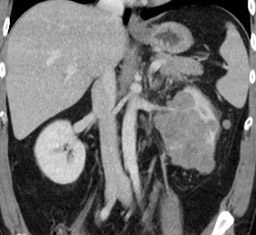

Carcinoma medular renal.

El carcinoma medular renal es una variedad de tumor renal muy infrecuente, diagnosticándose en fase avanzada metastásica y presentando un pronóstico nefasto a corto plazo. No existen directrices claras acerca de su manejo por la escasa evidencia sobre esta entidad. Presentamos un caso de un paciente afecto de carcinoma medular renal.